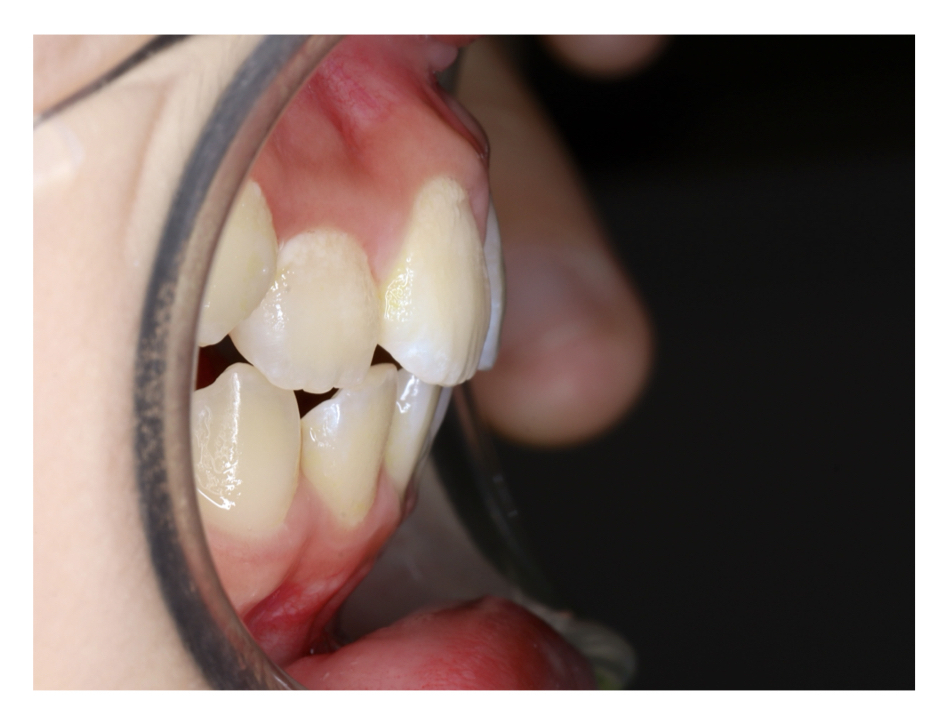

Case1

Before

After